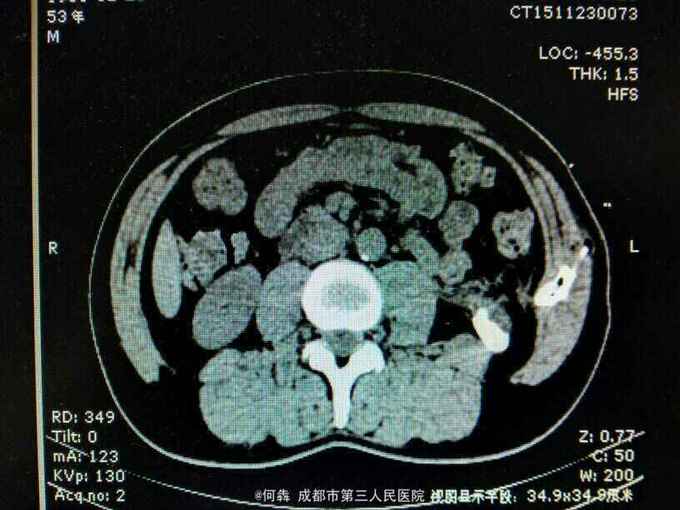

53岁,男性,因“腹腔镜下双肾囊肿切除术后1年余,左腰部窦道形成10月余”入院。无高血压病及糖尿病。

左腰部窦道形成伴少许脓液。窦道脓液培养出绿脓杆菌。

腹腔镜双肾囊肿切除术后窦道形成伴感染。现使用敏感抗生素派拉西林舒巴坦抗感染。